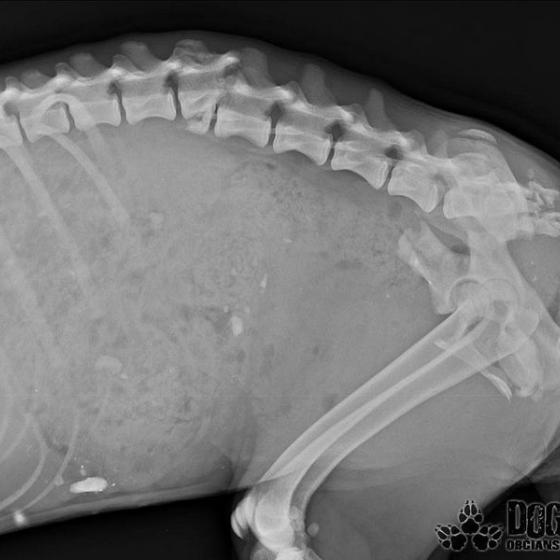

Mira, tak sme ju pomenovali.. Bola jednoducho úžasná.. Stalo sa však jedného dňa, že ju opustili.. Opustili a nechali napospas krutému osudu.. Nechápala a vybrala sa teda hľadať svojho človeka tam, kde ich bolo najviac.. Na vlakovú stanicu.. Vtedy ešte nepoznala ľudskú ľahostajnosť, iba lásku išla rozdávať.. Dni ubiehali jeden za druhým a nikto si po ňu neprišiel, nikto jej nepomohol.. Nenašiel sa ani jeden človek, ktorý by ju vzal do bezpečia pred rýchlym vakom.. V nepozornosti vybehla na koľajnice práve vtedy, keď vlak prichádzal.. Nie, ani po zrážke s vlakom jej nikto nepodal pomocnú ruku.. Musel ubehnúť týždeň, kým sa našla jediná dobrá duša, ktorá privolala pomoc.. Toto mladé a úchvatné dievčatko prežilo jeden celý týždeň s rozmliaždenou panvou, zlomenou chrbticou a poranenou miechou.. Neprestalo však čakať na svojho človeka, neprestávala dúfať, chcela žiť! Ľudia ju však iba obchádzali a odháňali..

Pomoc pre Miru žiaľ prišla neskoro.. Dnes poobede vraj ešte ako tak stála na nohách, ale večer okolo 22:00 keď sme dorazili, sa už postaviť nevedela. Našli sme ju zalezenú a premrznutú v plechovej búde.. Nedokázala si udržať stolicu, nedokázala sa samostatne vymočiť.. Miecha sa jej roztrhla.. Okamžite sme s ňou utekali do Bratislavy na kliniku, ale bolo neskoro.. Miruška musela mať neznesiteľné bolesti, ale tíško čakala a verila, lebo konečne bol pri nej človek, ktorého tak zúfalo hľadala..